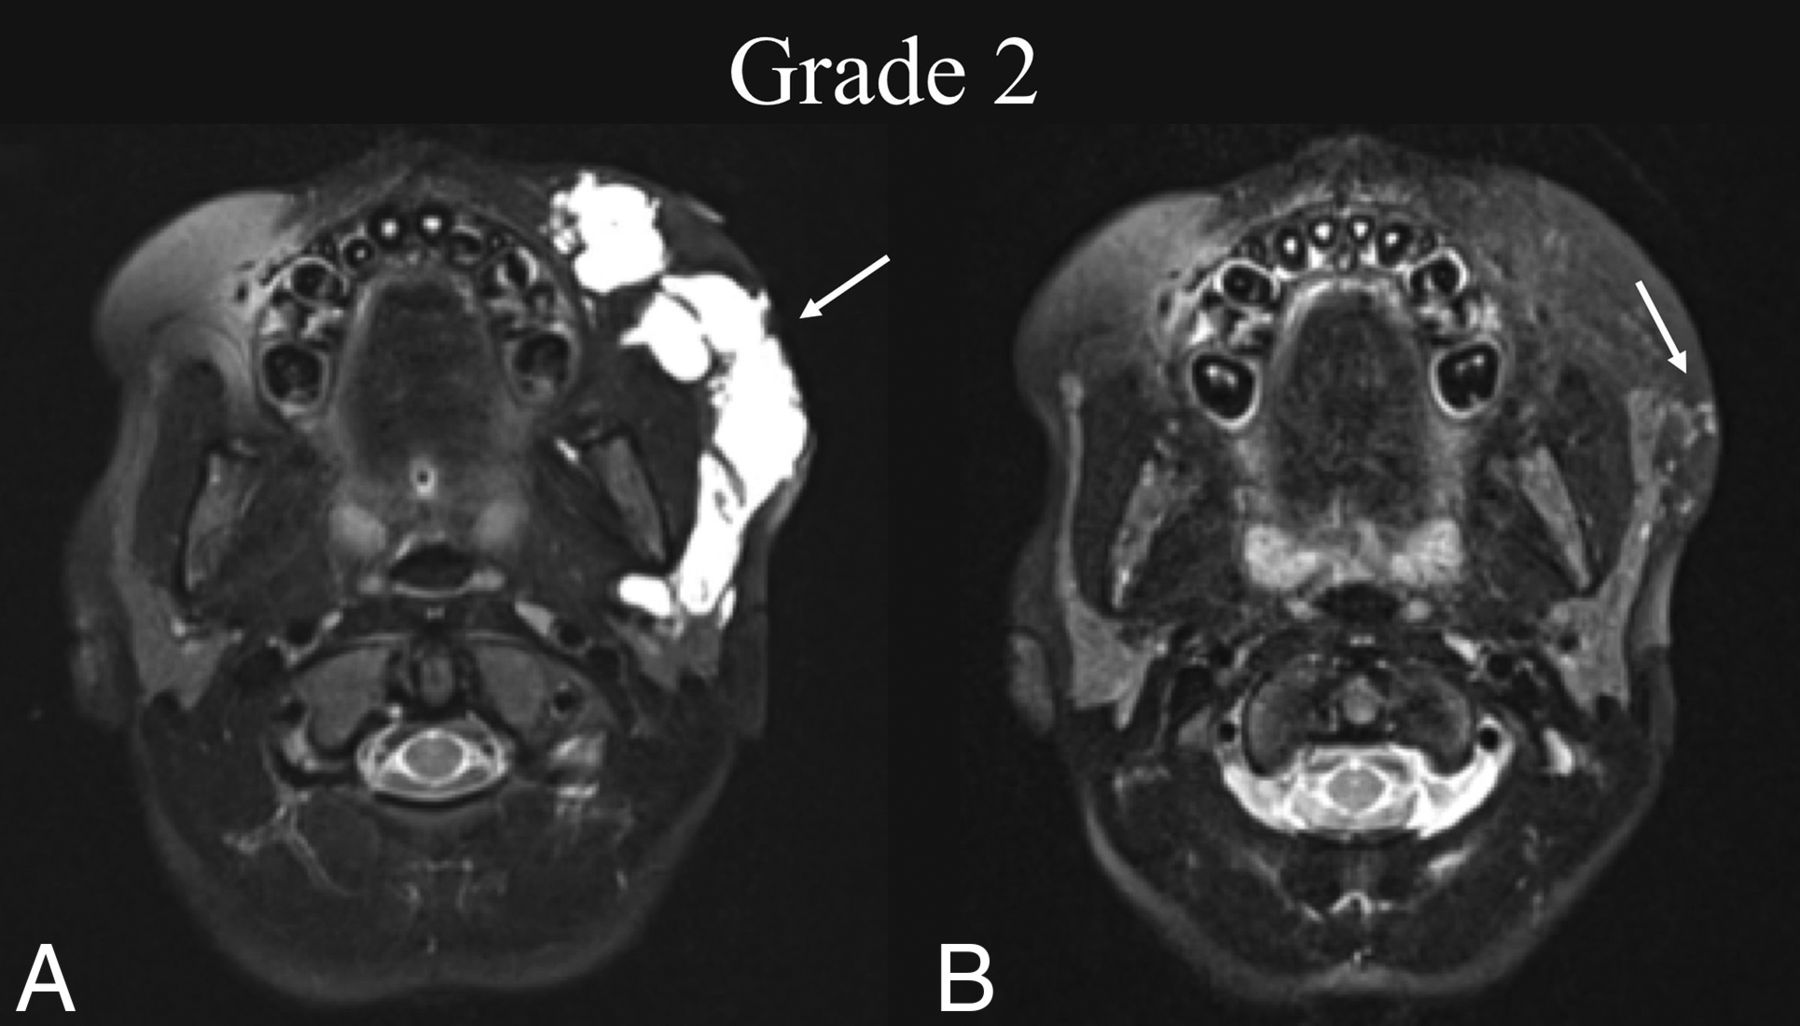

BDL grade 2 response. A 7-year-old girl with a left cheek mass was found to have a de Serres stage II mixed macro-/microcystic LM of the head. A, Preprocedural T2 fat-suppressed axial MR imaging at the level of the maxillary alveolar process shows involvement of the left buccal and parotid spaces (white arrow). B, Seven months later, following 2 sclerotherapy treatments, T2 fat-suppressed axial MR imaging at the same level shows BDL grade 2 near-complete resolution of the LM with trace residuals (white arrow).